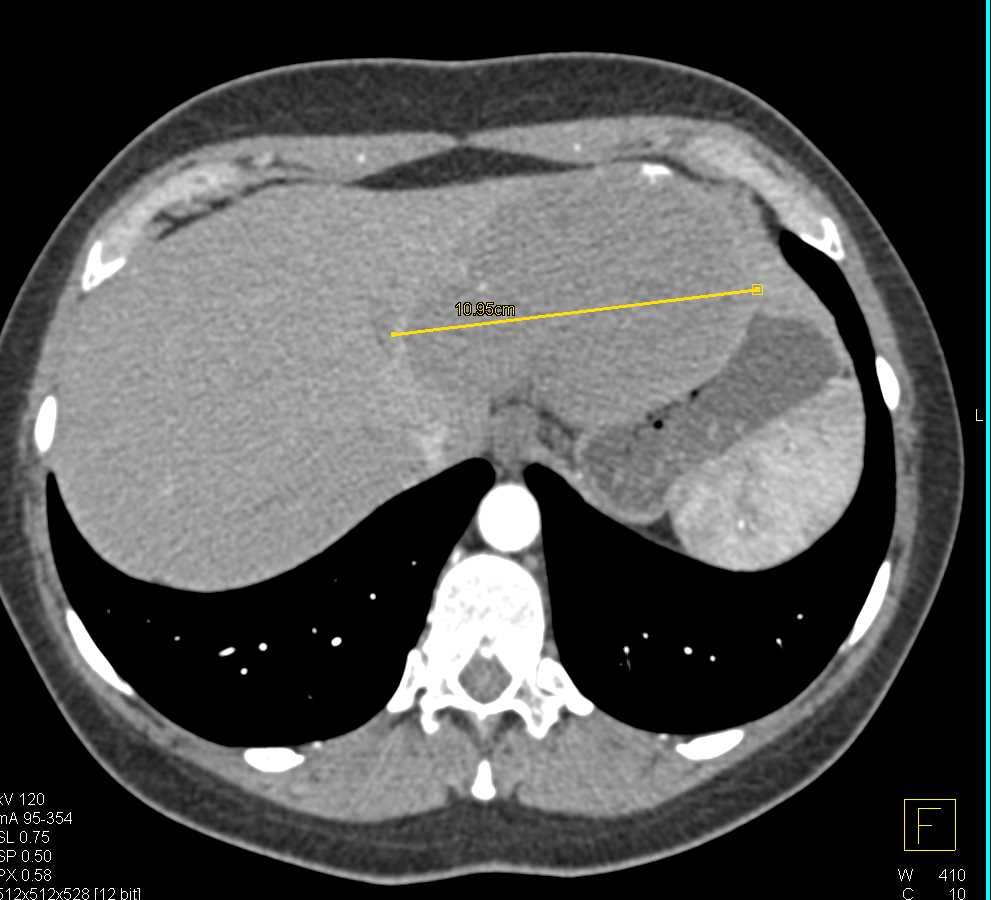

Adenocarcinoma Tail of Pancreas with Liver Metastases